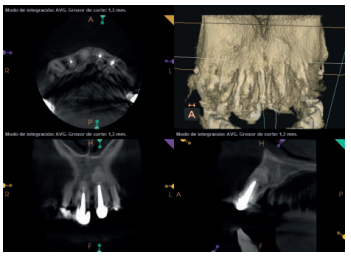

Para confirmar el origen endodóntico y el tamaño de las lesiones se realizaron exploraciones tomográficas con espesor de corte de 75 micras mediante CBCT CS8100 (Carestream Dental® ) en las que se evidenciaron lesiones periapicales radiolúcidas a nivel de 12, 11, 21 (con afectación bicortical), 25 y raíces vestibulares de 26 (Figuras 4 a 8).